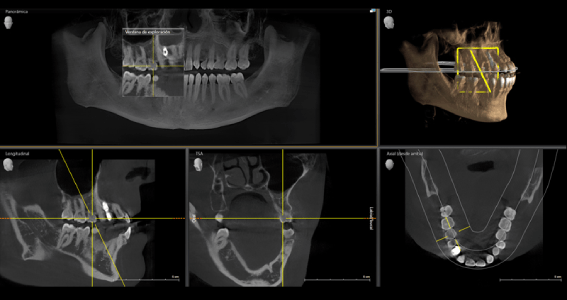

Scanner / Cone Beam / Tomografía 3D

- Maxilar

- Mandíbula

- Bimaxilar

- diente o zona específica

- Cavidades paranasales

- Cráneo completo (TAC maxilofacial)

- ATM (boca abierta, cerrada o ambos)